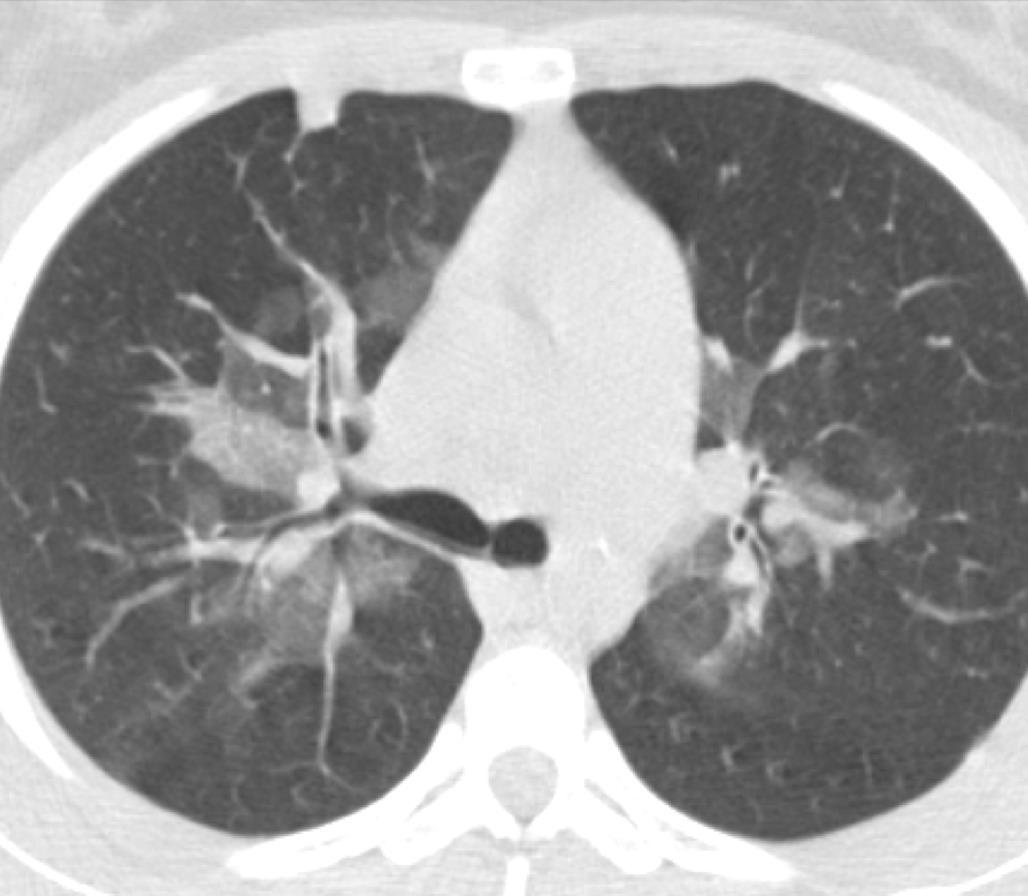

Acute Pediatric COVID-19: CT

3 Phases

Progressive: Diffuse GGO

Developed: Consolidation

Surr vasc congestion

Inflammation - adj alveoli

Alveoli fill with fluid/cells

Apicale sinistraa Medio -Basale sinistra

Basale sinistra Basale sinistra